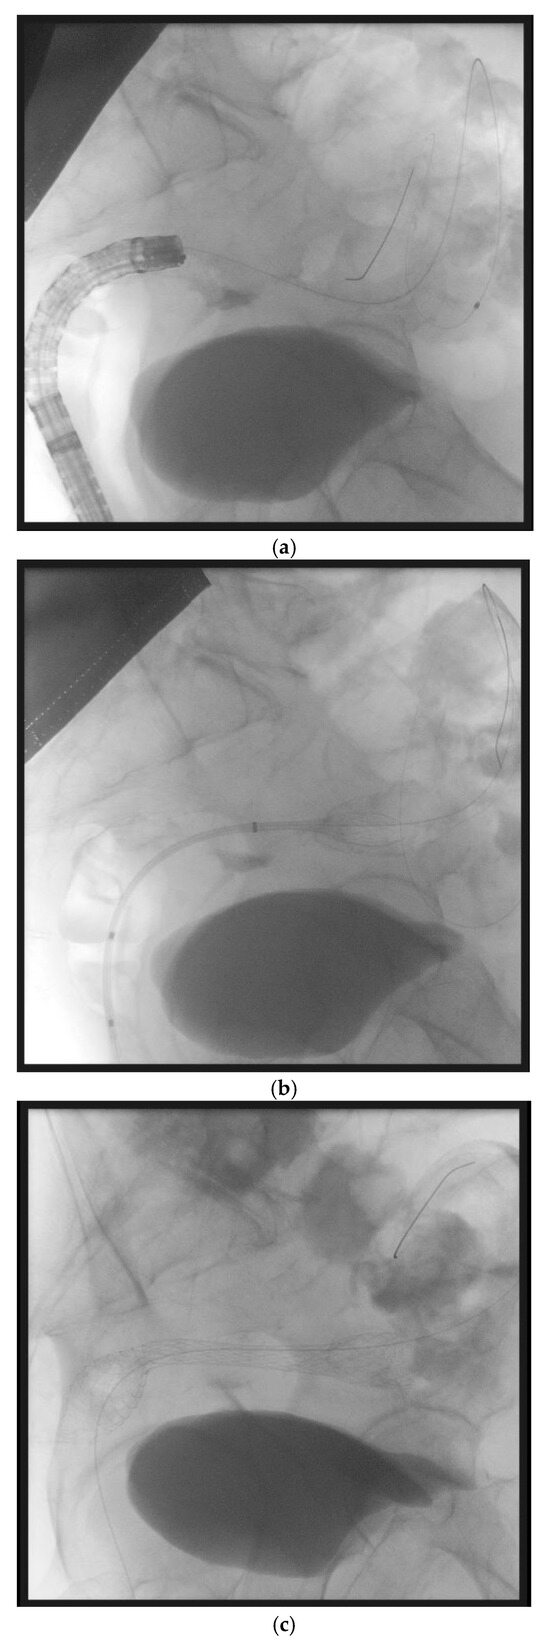

10. Endoscopic Ultrasound-Guided Entero-Colostomy with LAMS